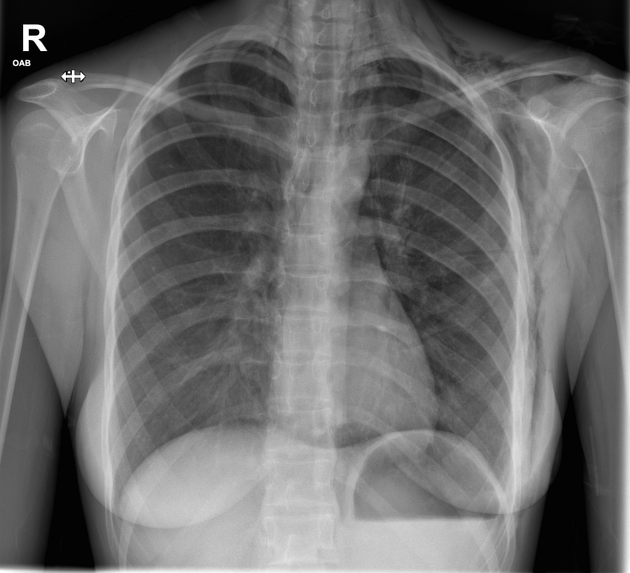

Describe the abnormality demonstrated.

Consolidation in the lower zone of the right lung. Obscuration of the right heart border (silhouette sign) and preservation of the right hemidiaphragm alludes to consolidation in the right middle lobe.